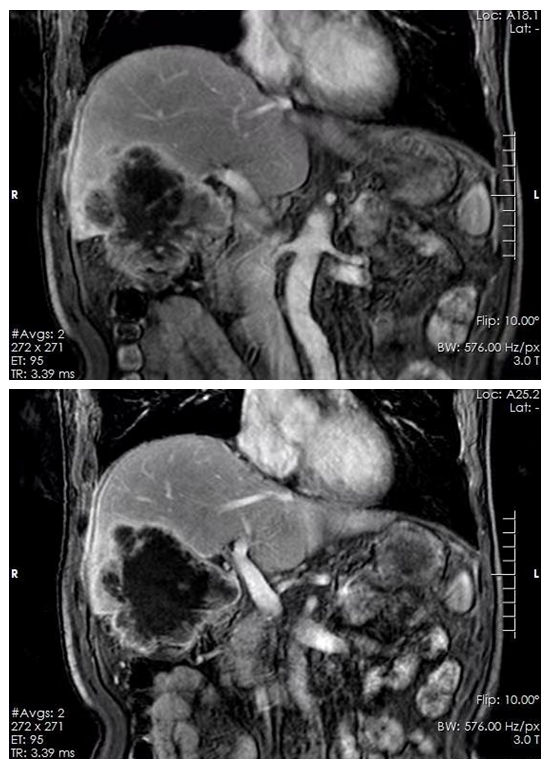

7月6日上午,麻醉科副主任王南海順利為患者完成誘導(dǎo)麻醉、氣管插管,術(shù)中,鄭翔主任和喻大軍主任發(fā)現(xiàn)原發(fā)腫瘤位于橫結(jié)腸肝曲,呈潰瘍型,已經(jīng)侵犯漿膜及周圍組織,還侵犯了十二指腸球降部外膜。腫瘤向上轉(zhuǎn)移至右肝Ⅴ段和Ⅳ段部分,同時(shí)侵犯了膽囊,并穿孔至肝組織,周圍有膿液。此外,腫瘤還侵犯了右側(cè)膈??;腸系膜血管周圍淋巴結(jié)腫大等一系列復(fù)雜情況。手術(shù)歷經(jīng)4個(gè)半小時(shí),成功切除了整塊結(jié)腸腫瘤及受侵的肝臟膽囊,并進(jìn)行了回腸橫結(jié)腸功能性端吻合。這是一項(xiàng)復(fù)雜的手術(shù),需要醫(yī)生的高超技術(shù)和勇氣。術(shù)后一周,患者順利出院。